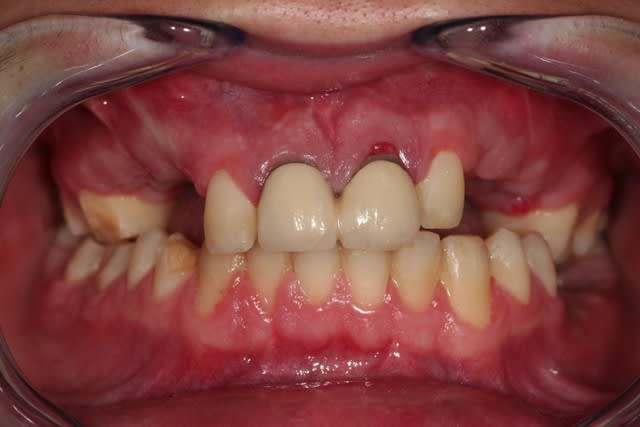

11 et 21 sautent de toute façon.

je pensais garder les deux latérales.

après, en garder une.

ensuite aucune.

Si tu avais une photo du sourire, des dents antérieures de face et des rétroalvéolaires des incisives supérieures, ce sera sympa. D'autre part, la 22 a-t-elle un son normal à la percussion ? Merci d'avance.

les images comme prévu.

son normal à la percussion, à part les cris du patient.

Sourir idgyv3 - Eugenol

12 cbn0ed - Eugenol

22 llsypc - Eugenol

Si les centrales sont asymptomatiques et de mobilité normale, est-ce que ça ne pourrait pas valoir le coup de tenter de les garder ? Tu ne voudrais pas démonter les couronnes et ré-évaluer notamment la 21 avant de tout dégager ?

La 22 semble fracturée sur la pano, mais c'est peut être un artefact, il faudrait vérifier avec une rétro, mais si c'est le cas, tu es évidemment mal barré pour une traction.

Dans tous les cas, si tu conserves la 22, surveille la pendant quelques mois avec des rétros pour t'assurer de l'absence de résorption.